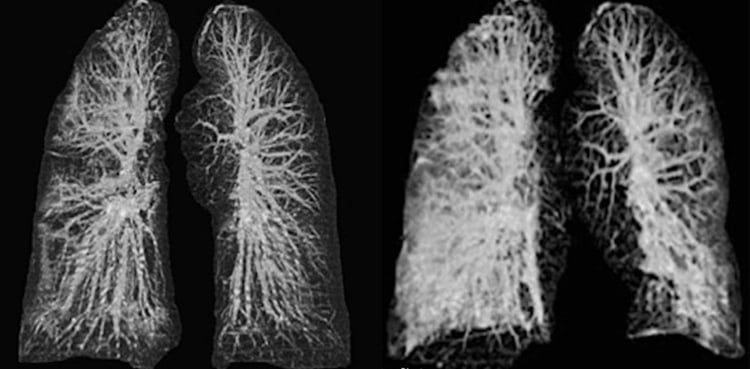

As the world grapples with the coronavirus pandemic, shocking images have emerged of the lungs of two victims of COVID-19.

The images show how the virus affected the lungs of the Wuhan residents in their 60s on holiday in Italy.

The 67-year-old man and 65-year-old woman were the country’s first recorded victims of the disease.

X-ray scans and CT images reveal how COVID-19 took its serious toll on their lungs and respiratory system in a similar but distinct way to both SARS and MERS.

Early x-ray images revealed “ground-glass opacities” — where air spaces in their lungs become filled with a substance, usually pus, blood or water.

Ground-glass opacity is frequently associated with the thickening or swelling of soft tissue, known as consolidation.

A phenomenon called crazy paving was also seen, which indicates thickening of the septum and intralobular septum, which can inhibit performance.

Patients with COVID-19 have shown fluid or debris-filled sacs in the lungs, which may get progressively worse as the illness develops.

The study also discovered the blood vessels taking blood from the heart to the lungs to become oxygenated were becoming enlarged.

This increased size, known as hypertrophy, reduces the space for air in-between, causing difficulty breathing and respiratory problems.

This sign is likely to be related to the hyperemia — excess blood in the lung’s vessels — caused by the viral infection.

The researchers write: “Lung patterns in both patients were characterised by hypertrophy of the pulmonary vessels, which are increased in size, particularly in areas with more pronounced interstitial impairment.

“This new radiological evidence suggests a different pattern of lung involvement compared to those observed in the other known severe coronavirus infections (SARS and MERS).”